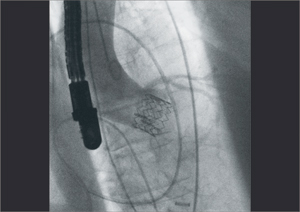

Ziehm Vision RFD - уникальный мобильный рентгеновский аппарат с возможностью многостороннего клинического применения. Плоскопанельный детектор аппарата дает отличные высокоточные изображения, обеспечивая прекрасную визуализацию для инвазивной радиологии, нейрохирургии, сосудистой хирургии, кардиологии и при инвазивных процедурах, таких как аневризма абдоминальной аорты или ЧТКА, и находит также применение в гибридных областях,

как например, при имплантации аортального сердечного клапана.

Ziehm Vision RFD - уникальный мобильный рентген с плокопанельным детектором для многостороннего клинического применения. Аппарат дает отличные высокоточные результаты в инвазивной радиологии, нейрохирургии, сосудистой хирургии, кардиологии и при инвазивных процедурах, таких как аневризма абдоминальной аорты или ЧТКА, и находит также применение в гибридных областях, как например, при имплантации аортального сердечного клапана. Специальный программный пакет SmartVascular позволяет выполнять цифровую субтракционную ангиографию, в том числе с возможностью использования CO2 как контрастного вещества. Возможность установки дополнительных потолочных мониторов и внешнего интерфейса управления, а так же расширенное орбитальное вращение штатива делают Ziehm Vision RFD незаменимым аппаратом для многофункциональных операционных.